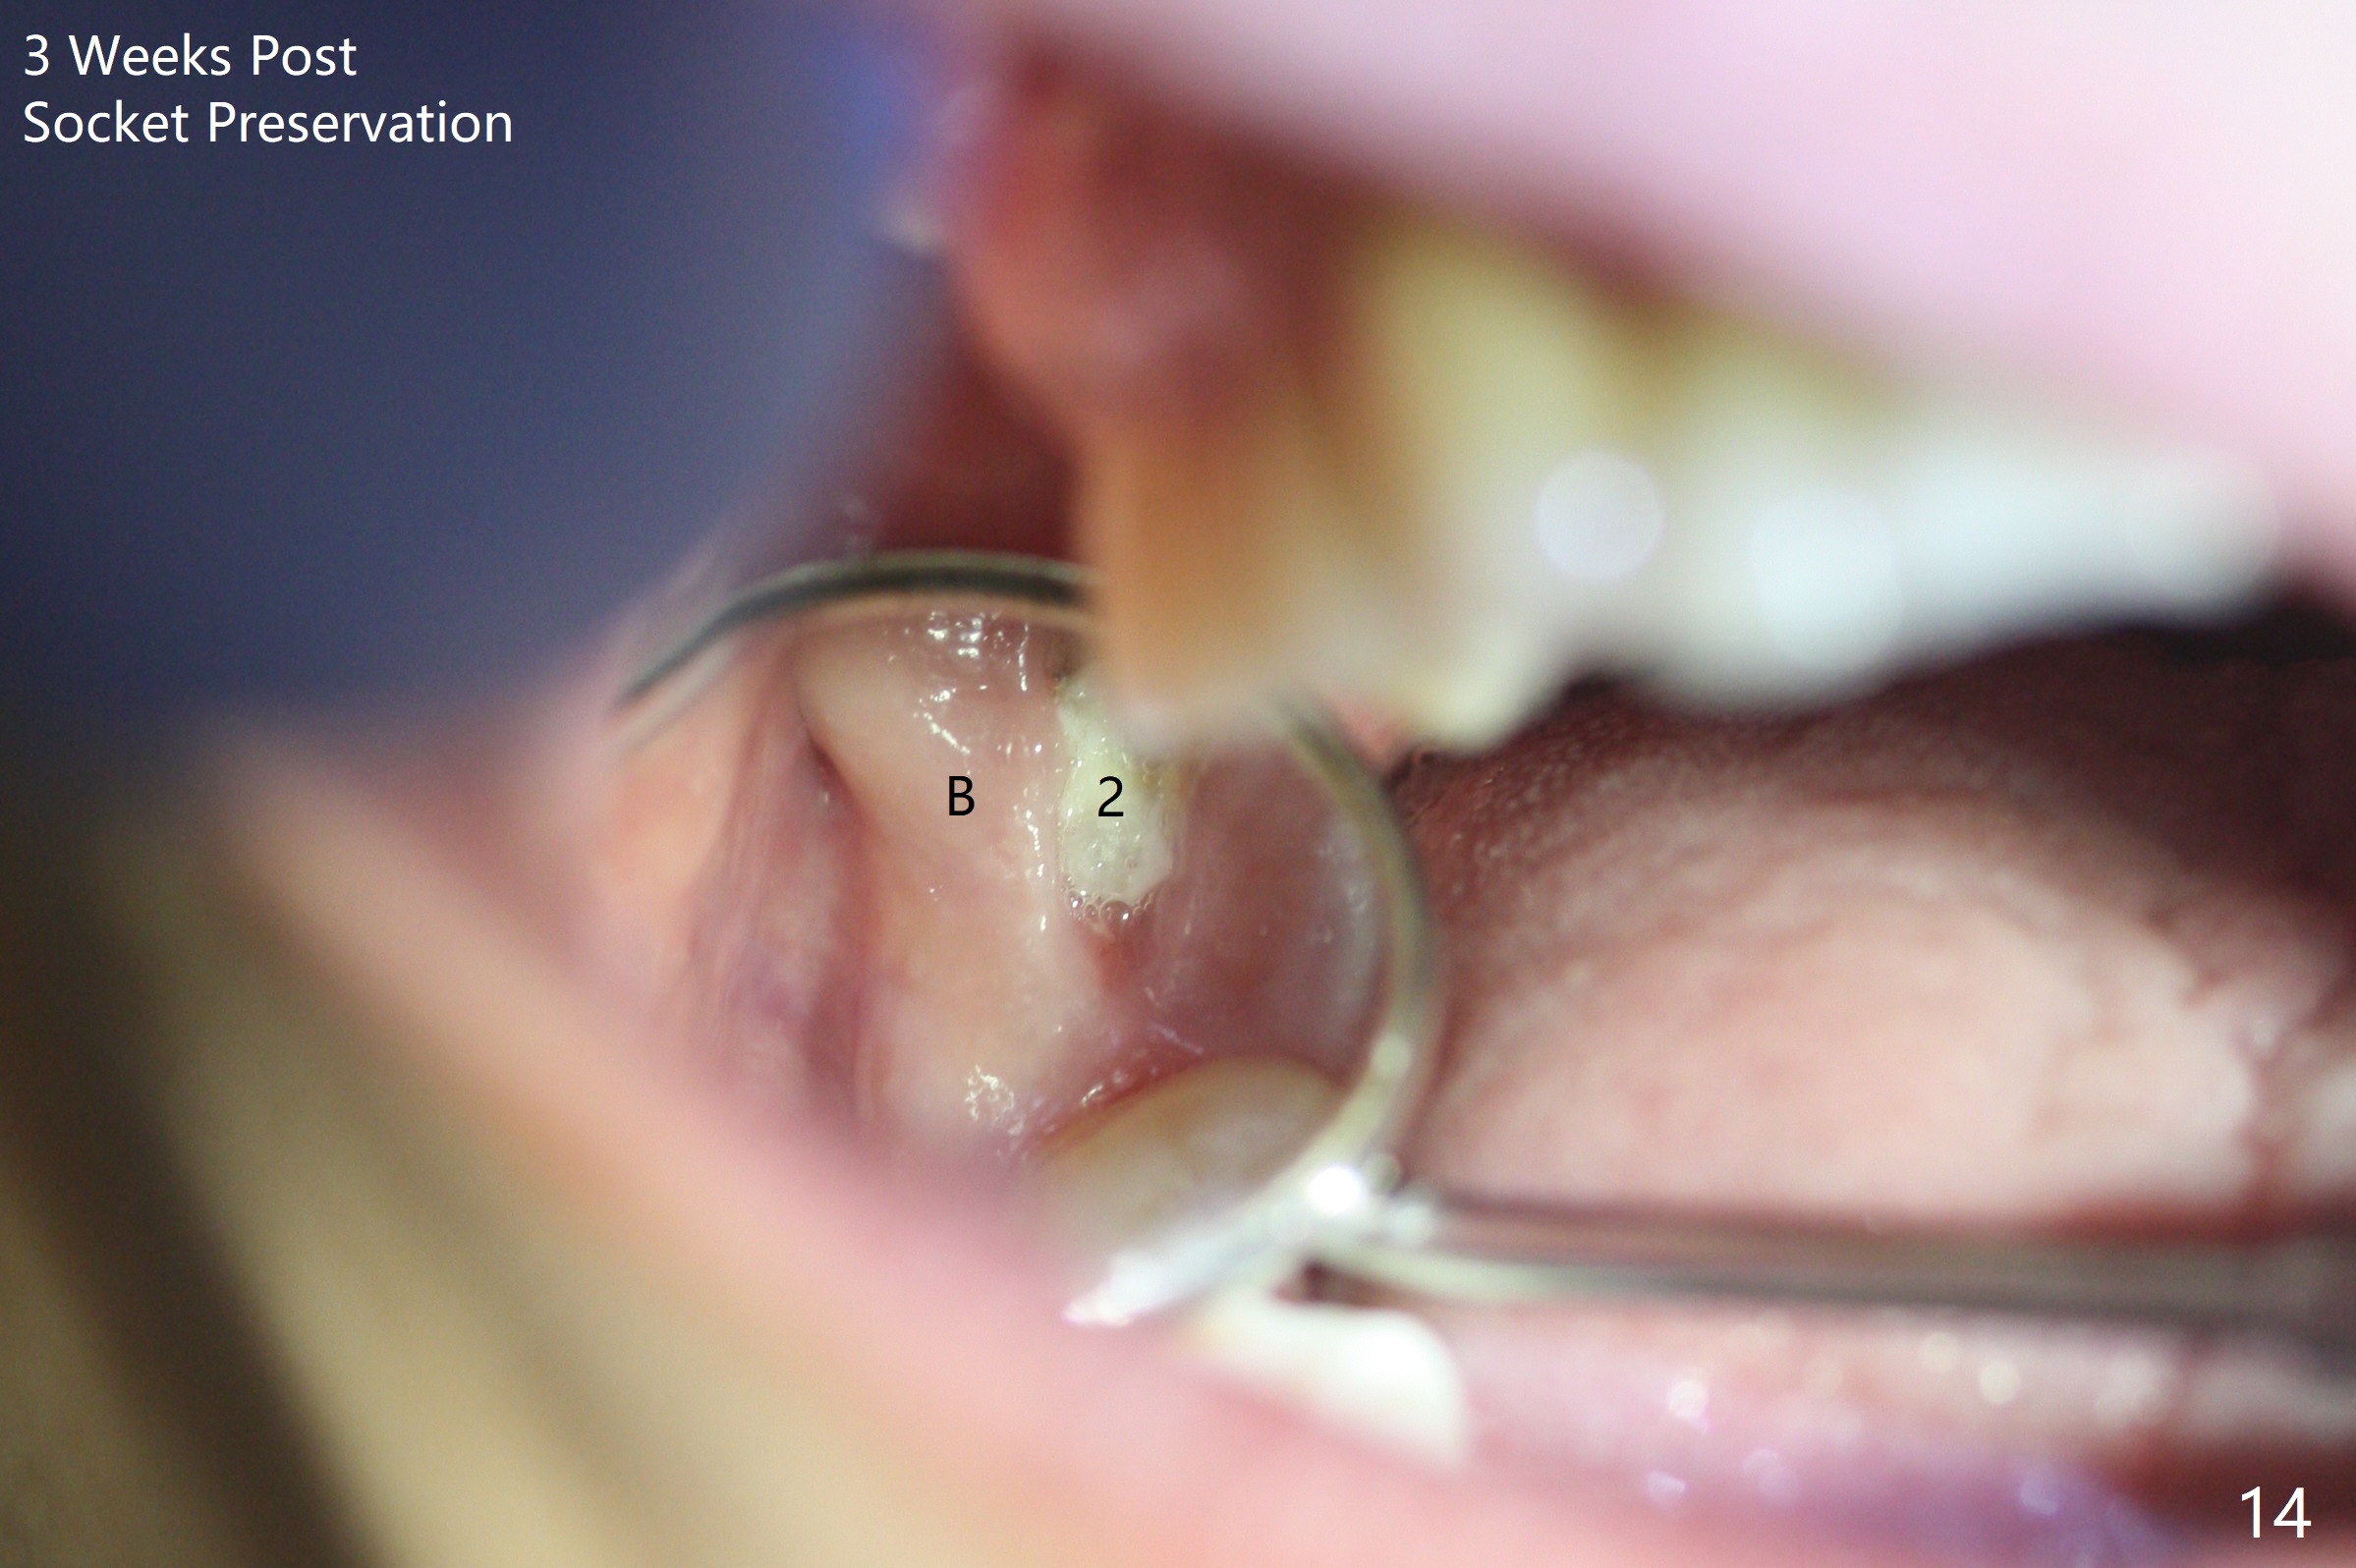

When the 59-year-old man returns for #24 implant placement, the tooth #2 is found to have crack (Fig.1,2 arrowheads), associated with buccal and palatal fistulae (*) and loss of amalgam (Fig.4 *). Abundant granulation tissue is attached to the roots of the affected tooth (Fig.3), indicating severe bone loss. There is a plateau associated with the septum and buccal sockets, which is the site of osteotomy. Magic split and 3 and 3.8 mm Magic Expanders are used to initiate osteotomy. After use of 4.3 mm Magic Drill for about 3 mm, Osteogen plug and allograft are used for sinus lift, followed by insertion of a 4.5x11 mm dummy implant (Fig.5). When a 5.5x9 mm dummy implant is placed with stability, it appears to be seated cervical (Fig.6,7). When a 6x9 mm IBS implant (definitive) is placed with a 6.5x5.5(4) mm abutment, they are seated too deep for provisional (Fig.8). The implant/abutment are removed and replaced by a 6.5x11 mm one in a shallower position; after trimming the same abutment as mentioned above (Fig.9), an immediate provisional is fabricated to keep bone graft in place. Fabrication of Tap with soft tissue markers will reduce the chance of miscalculation and waste of implants. The coronal threads of the implant are covered with bone 6 months postop (Fig.10). One month later when a permanent crown tries in, the implant is found to be loose and tender. A healing abutment is placed. Six months later, the patient returns for crown retry-in. The tooth #1 seems to have shifted mesially (Fig.11 arrow). When the abutment is placed, the implant remains tender and loose. After implant removal with a wrench, there is no granulation tissue or bony defect, including the intact sinus floor (Fig.12 <). Since the tooth #1 has deep periodontal pockets and mobility, the tooth is extracted with abundant granulation tissue. After debridement, Osteogen plug is placed in the socket of #1, while Vanilla graft is placed at the site of #2 (Fig.13 *). Three weeks later, the socket of #2 heals with exposure of Osteogen plug (Fig.14 (B: buccal)).